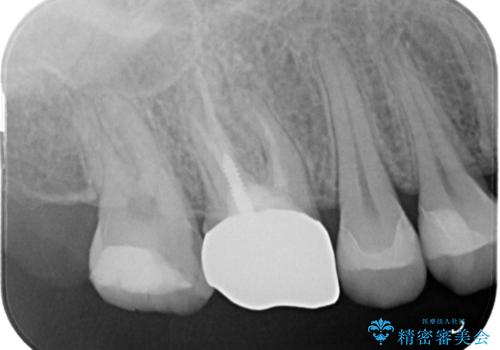

- 右上4、5間にフロスのひっかかりがあり、レントゲンから隣接面う蝕を確認しました。う蝕除去後は両歯にCADCAMインレーをセットしています。

歯の隣接面を正確に合わせることによって、物が詰まりにくく、再びう蝕になる確率を下げてくれます。